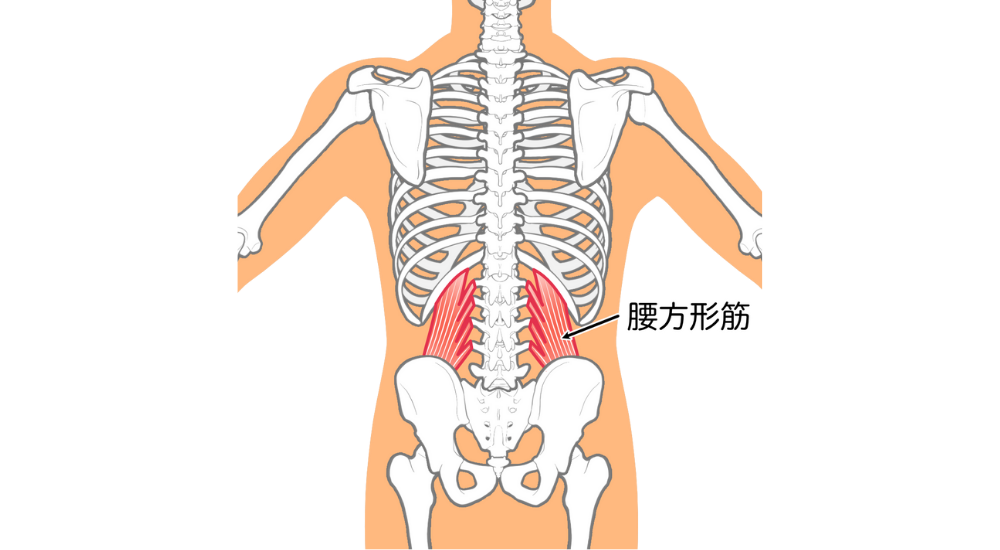

- 腰方形筋:

腰の深部にあり、体幹の側屈や安定に関わる。左右のバランスの崩れや不良姿勢で負担がかかりやすいです。